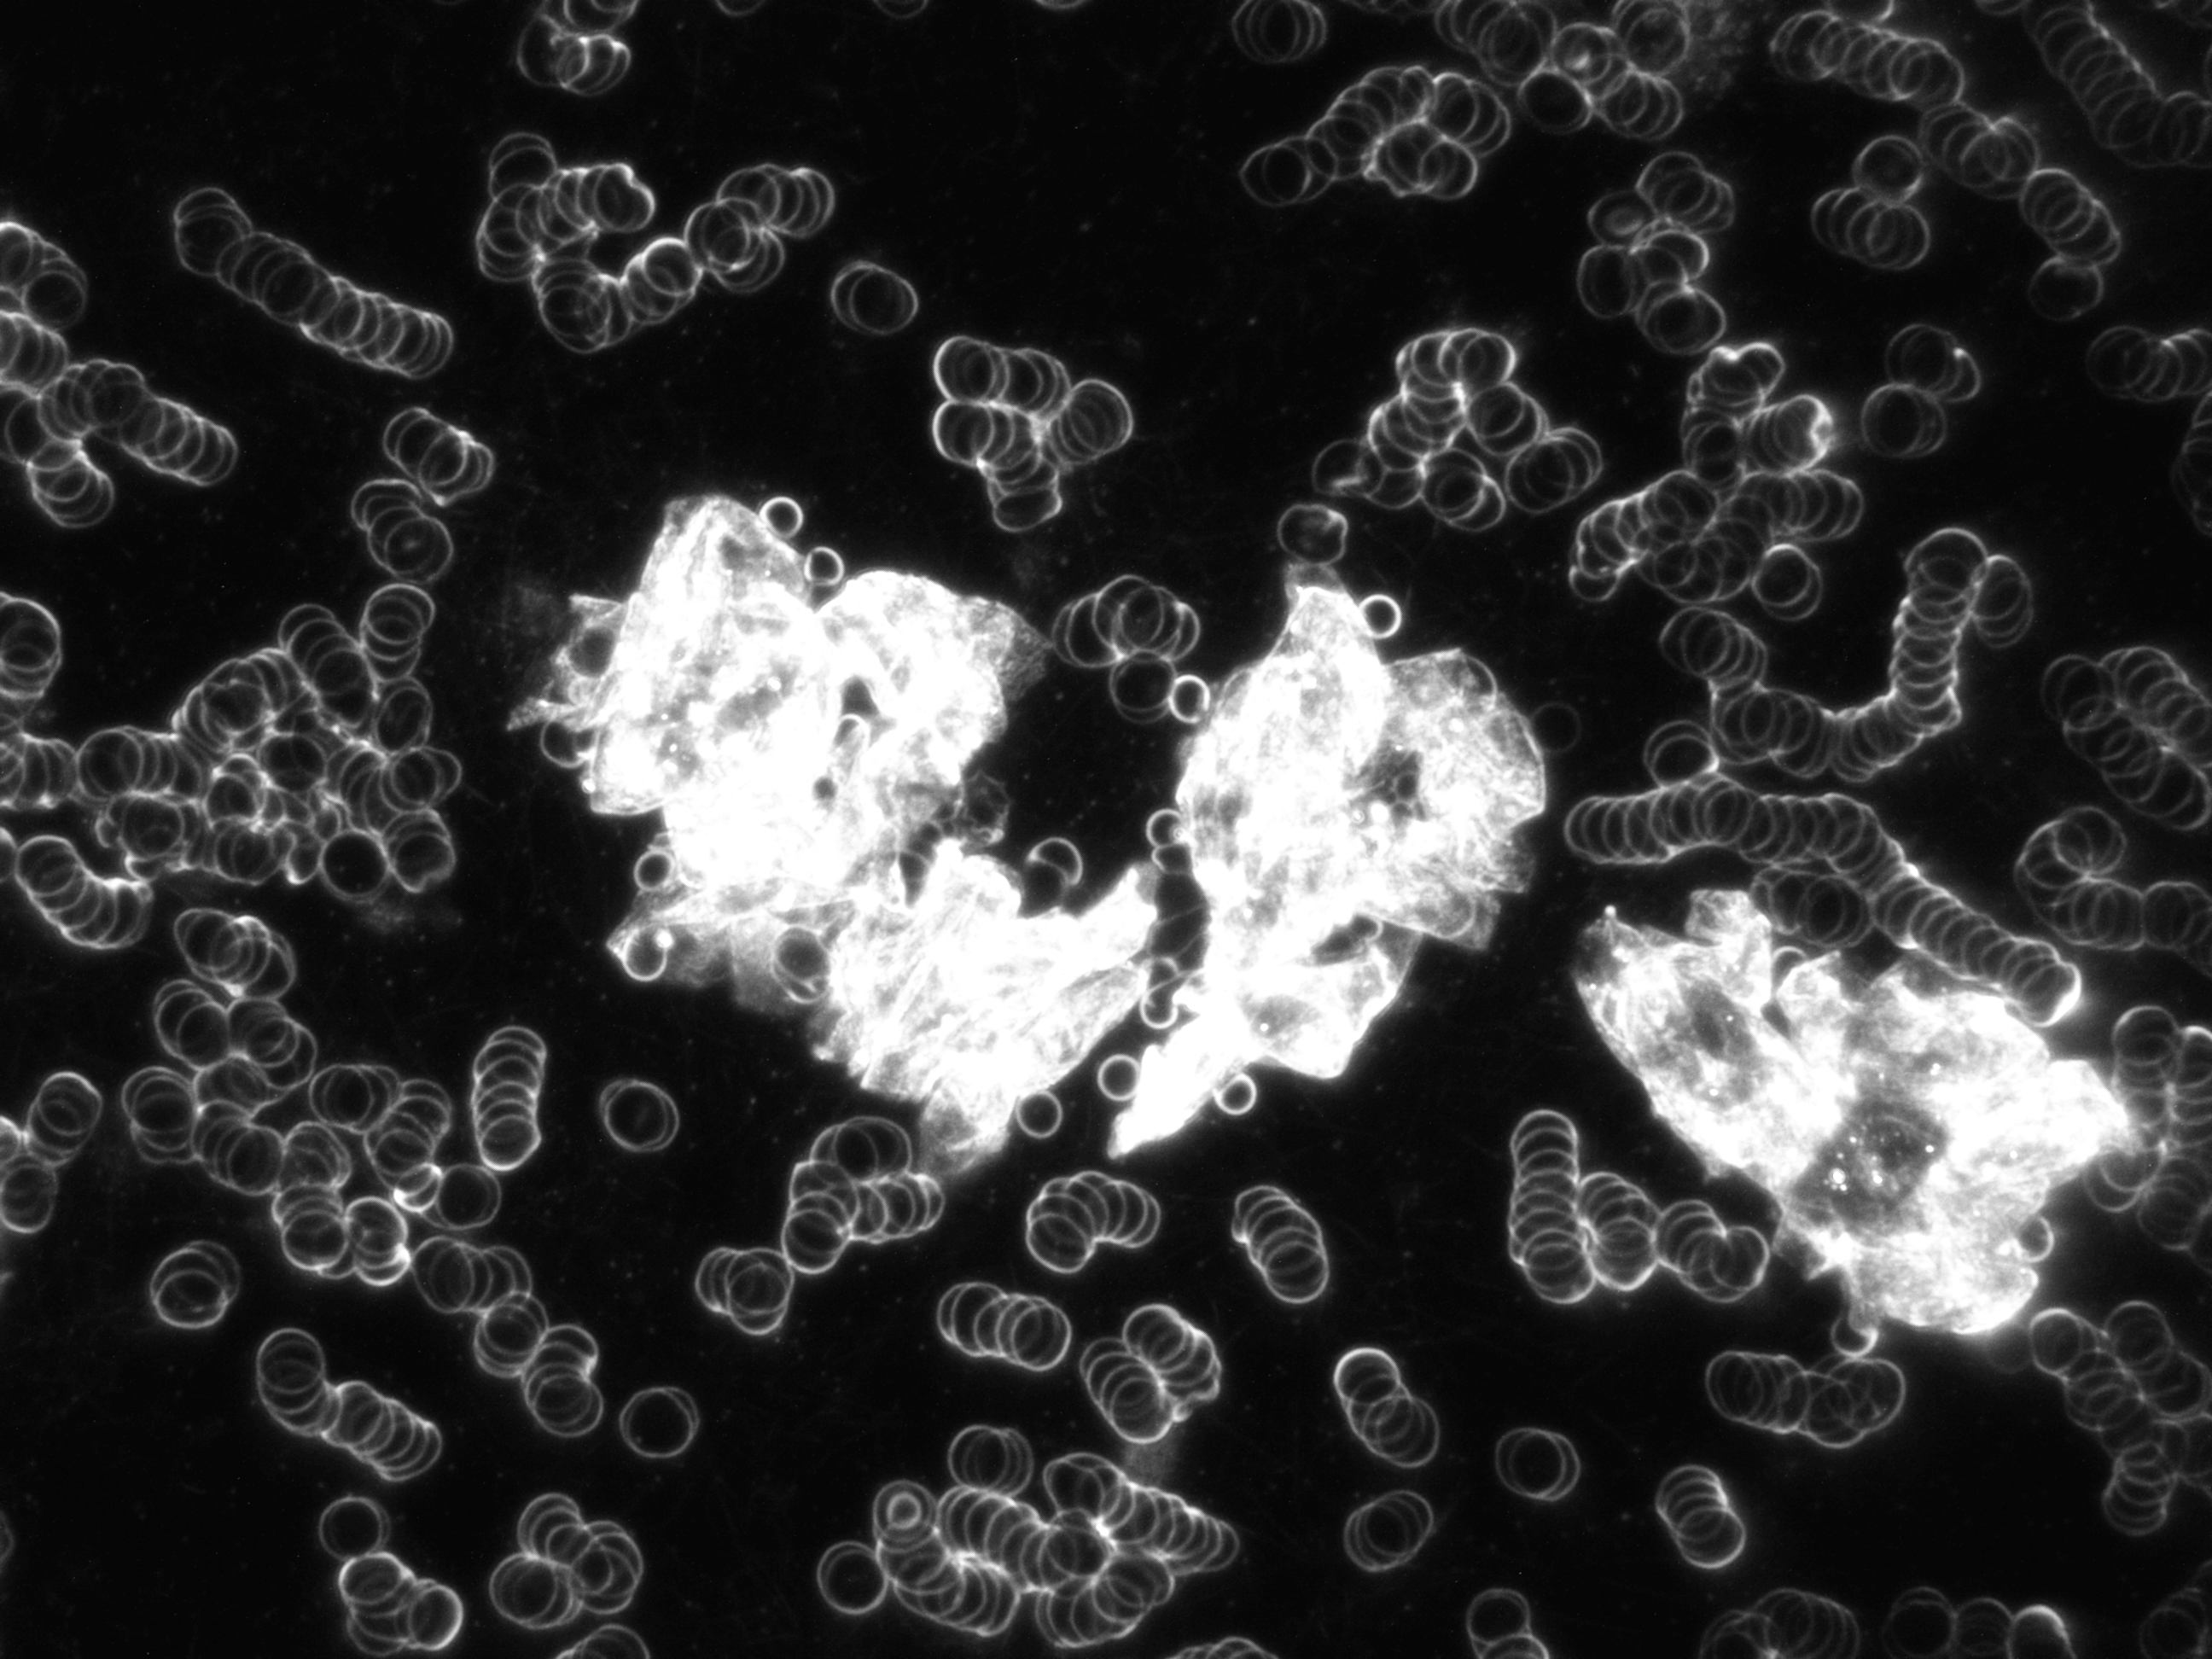

Vitalblutanalyse

Vitalblutanalyse

Vitalblut im Dunkelfeld Lichtmikroskop mit Geldrollenbildung

Vitalblut im Dunkelfeld mit diversen Auffälligkeiten

Symplast im Blut

Hier müssen mehrere Ebenen mit verschiedenen Schärfen betrachtet werden,

um eine Verunreinigung des Objektträgers auszuschließen